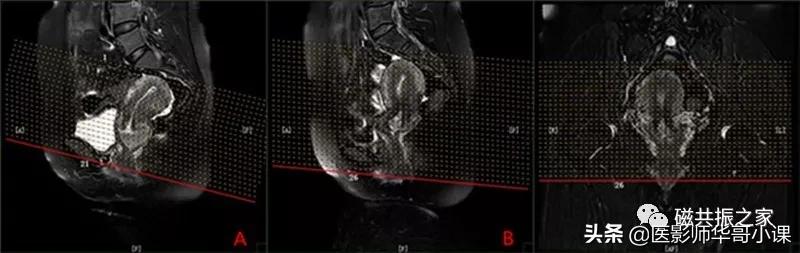

在冠状位和矢状位上定位,在矢状位上找到显示子宫全景最好的层面,如需了解宫颈病变,使定位线垂直于宫颈管长轴(图A),如需了解子宫内膜病变,使定位线垂直于子宫内膜长轴(图B)。在冠状位调整角度使两侧对称扫描,扫描范围上至子宫上缘下至耻骨联合,需包括整个病变范围,如观察转移性病变需加大扫描范围。

在横轴位和矢状位上定位,在矢状位上找到显示子宫全长最好的层面,如需了解宫颈病变,使定位线平行于宫颈管长轴(图A),如需了解子宫内膜病变,使定位线平行于子宫内膜长轴。在横轴位上找到显示子宫最大的层面,使定位线平行于当前子宫内膜长轴,扫描范围包括整个子宫及两侧附件,需包括整个病变范围。